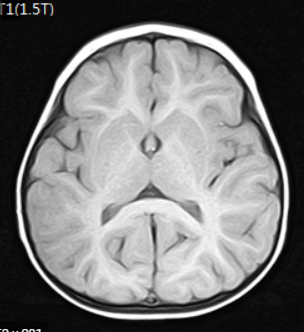

2018년 10월에 뇌 MRI 보험적용이 바뀌게 됩니다. 2018년 10월 이전에는 중증 뇌질환환자로 의사가 인정하는 경우에만 제한적으로 건강보험 적용이 되었습니다. 해당 상병으로는 뇌출혈, 외전증, 뇌경색 등이 있습니다.

하지만 2018년 10월에는 뇌혈관 및 뇌 MRI 가 건강보험 적용이 확대 되었습니다. 경증인 뇌질환이나 신경학적으로 이상이 있거나, 검사상 이상소견이 있다면 건강보험이 적용이 가능해졌습니다.

그리고 뇌질환이 의심되는 두통이 있거나, 어지러움이 있고 신경학적 검사를 실시한 경우에도 건강보험이 적용이 되어서 많은 국민들의 부담이 줄어들었습니다.